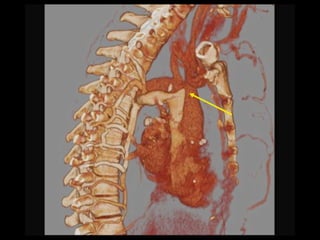

Paravertebral vv. Capsular /Liver surface vv. Systemic – portal collaterals

Venous collaterals organizedby plexus systems – Easier, more complete to report Cihangiroglu: J Comput Assist Tomogr, Volume 25(1).January/February 2001.1-8